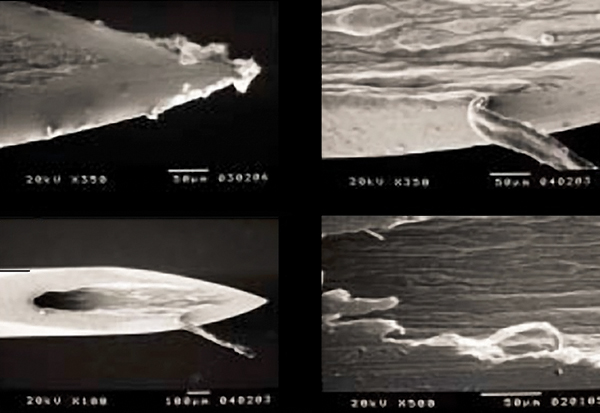

A needle with manufacturing defects is more likely to have existing, or easily created, barbing and splintering, which may result in issues with the penetration process of the needle, damage to soft and neuronal tissues, hemorrhage, or causing moderate to severe pain.34 During the manufacturing process, the cutting of the needle bevel can lead to irregularities in the stainless steel, which may result in these adverse outcomes (Figure 3). The creation of the irregularities is related to both the cutting process and the quality of steel being used.35

ISO (International Organization for Standardization) provides standards on the type of stainless steel as well as the minimum thickness of steel used in needle manufacturing. Because of organizations like ISO, manufacturing defects continue to decrease. However, defects still exist, especially on a microscopic level.35 In fact, a recent study evaluating the most commonly purchased needles found that the homogeneity in the metal alloys did not generally conform to international manufacturing guidelines.36 In addition, the authors concluded that a wide variation between applied standards exist and it appears that most manufacturers apply their own standards to the manufacturing process. Ultimately, the quality of material and the type of finish of the needle bevel is vital in decreasing the irregularities, which aids in decreasing barbing.34,35

Fig 3. Microscopic view of irregularities of unused dental needles (from: Sanchez DE, Fernandez RE. Microscopic assessment of dental needles. Guadalajara University. Used with permission.)

Figure 3